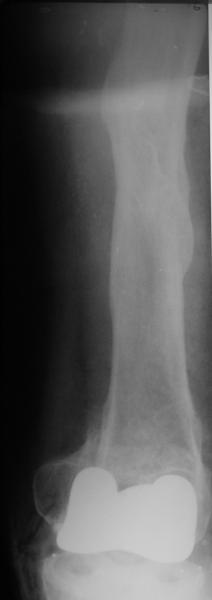

Дистальный перелом бедра после эндопротезирования. |

Добрый день! В нашу больничку поступил пациент после бытовой травмы - упал, подвернув ногу. На RG-граммах перелом дистального метаэпифиза бедренной кости. Пациент спутанно рассказывает, где и как он лечился раньше.10 лет назад - коррегирующая остеотомия по поводу деформирующего артроза коленного сустава, 3 года назад в 1 градской больнице г. Москвы выполнено эндопротезирование коленного сустава,площадка большеберцовой кости, со слов пациента, деформировалась около года назад (на фоне остеопороза). Сейчас получил травму в результате падения с высоты собственного роста.Что посоветуете?

Видимо, самое "модное" на сегодня - малоинвазивный остеосинтез пластиной с угловой стабильностью. Распространенный вариант и закрытый интромедуллярный остеосинтез ретроградно. Хотя у нас было бы сделано антеградно - лешево и сердито, действительно малоинвазивно, в сустав не надо влезать. Нет риска прорезания порозной кости с миграцией в сустав, что возможно при ретроградном - гвоздь вводится через вырез в бедреннм компоненте, туда же может и вывалиться. А антеградный - упрется в протез. Как раз вчера заходил больной через полтора года после такой операции. Снимки в приложении.

на снимке признаки loosening и тибиального и феморального компонентов я думаю нужна ревизия если нет возможностей то артродез и конечно исключить инфекцию . успехов .

Мне представляется следующее: Если дистальный отдел бедра расколот и в сагиттальной и во фронтальной плоскостях, как видно на рентгенограммах, и при этом есть смещение отломков относительно друг друга и бедренного компонента эндоаротеза, разве от может оставаться стабильным? В случае отсутствия проблем с тибиальным компонентом, можно было бы надеяться только на остеосинтез и стабилизацию, но если предполагается ревизия в ближайшие месяцы/год, то не лучше ли за один раз решить несколько проблем?